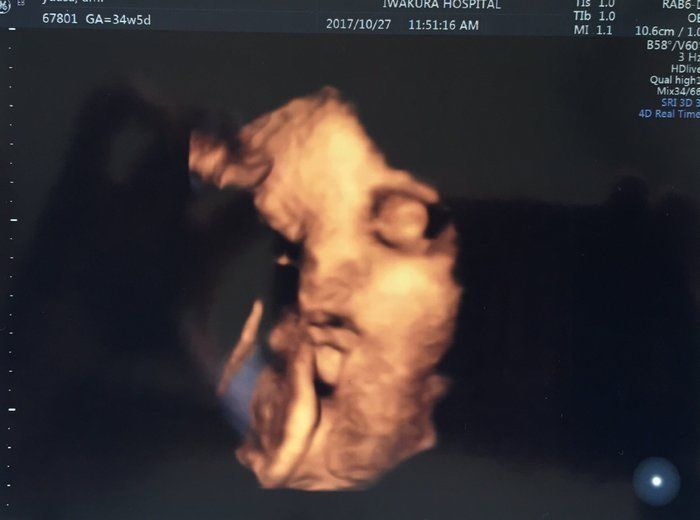

セイコさんの妊娠34週目のエコー写真 里帰り出産のため実家の産院へ移る

こちらの産院だと毎回4Dが撮ってもらえるので、楽しみです。かわいらしい手が結構はっきり写っています。手もほっぺもだいぶぷっくり?体重は2160g、頭の大きさは8.5㎝だそうです。

同じ日ですが、こちらはすごい顔で写っています。この週末は産院で行われた「パパママ育児クラス」に夫婦で参加しました。オムツの替え方、沐浴のさせ方、新生児に関するお話などを聞き、いよいよ本格的に出産の準備。パパたちが率先して挑戦していたのが、ほほえましかったです。